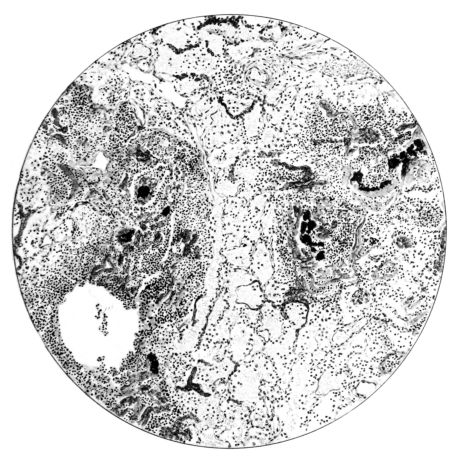

FIG. II. AUTOPSY NO. 98. DRAWING OF A SECTION THROUGH A TRACHEA SHOWING NECROTIZING HEMORRHAGIC INFLAMMATORY PROCESS OF THE MUCOSA.

The changes are less marked, perhaps, in the trachea than in its finer ramifications. The mucosa is constantly more or less destroyed and large areas, usually focal, are entirely devoid of their epithelial covering. This is replaced by a sparse exudate, composed largely of red blood cells, mucus, a small amount of fibrin, and nuclear fragments (Fig. II). It may dip into the submucosa for a short distance, but usually these indentures are associated with the ducts of the mucous glands into which the inflammatory reaction extends. A more striking feature than the exudate, however, is the edema and the congestion of the submucosa. The loose areolar tissue of the submucosa is spread widely apart, and throughout it distended blood vessels are very conspicuous. Occasionally such a vessel is broken and actual hemorrhage appears in the submucosa. Occasionally, too, the inflammation extends down the duct to the mucous gland itself, and here, also, aplastic inflammatory reaction is evident, inasmuch as the acini now stain intensely red with the cells undifferentiated from each other and specked here and there by broken remains of the dead nuclei (Fig. III). After the disease has continued for a short period, even at the end of five or six days, some regeneration of the epithelial lining may be seen (3) (Fig. IV). But despite this, the acute picture persists, and there goes on, side by side, an attempted repair characterized by epithelial regeneration and the same evidence of acute change. Since the lesion is essentially a superficial one, scars or contractures of any extent are not encountered in the trachea, even in examples of the disease that have ended fatally only after many weeks.[4]